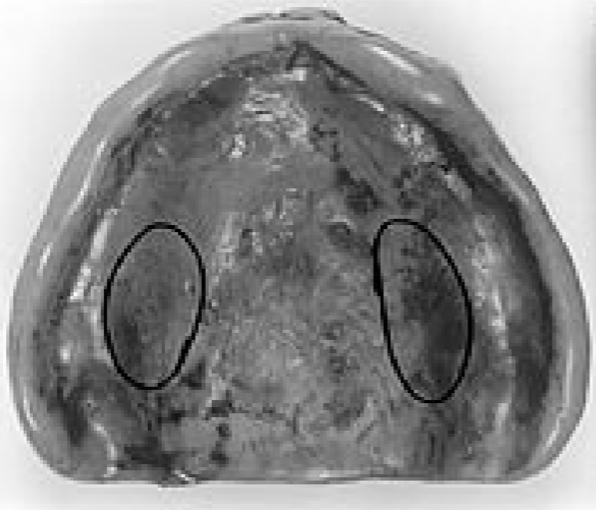

- Slide 1-3: Numbers on dentures

- Slide 4: Top view of dentures